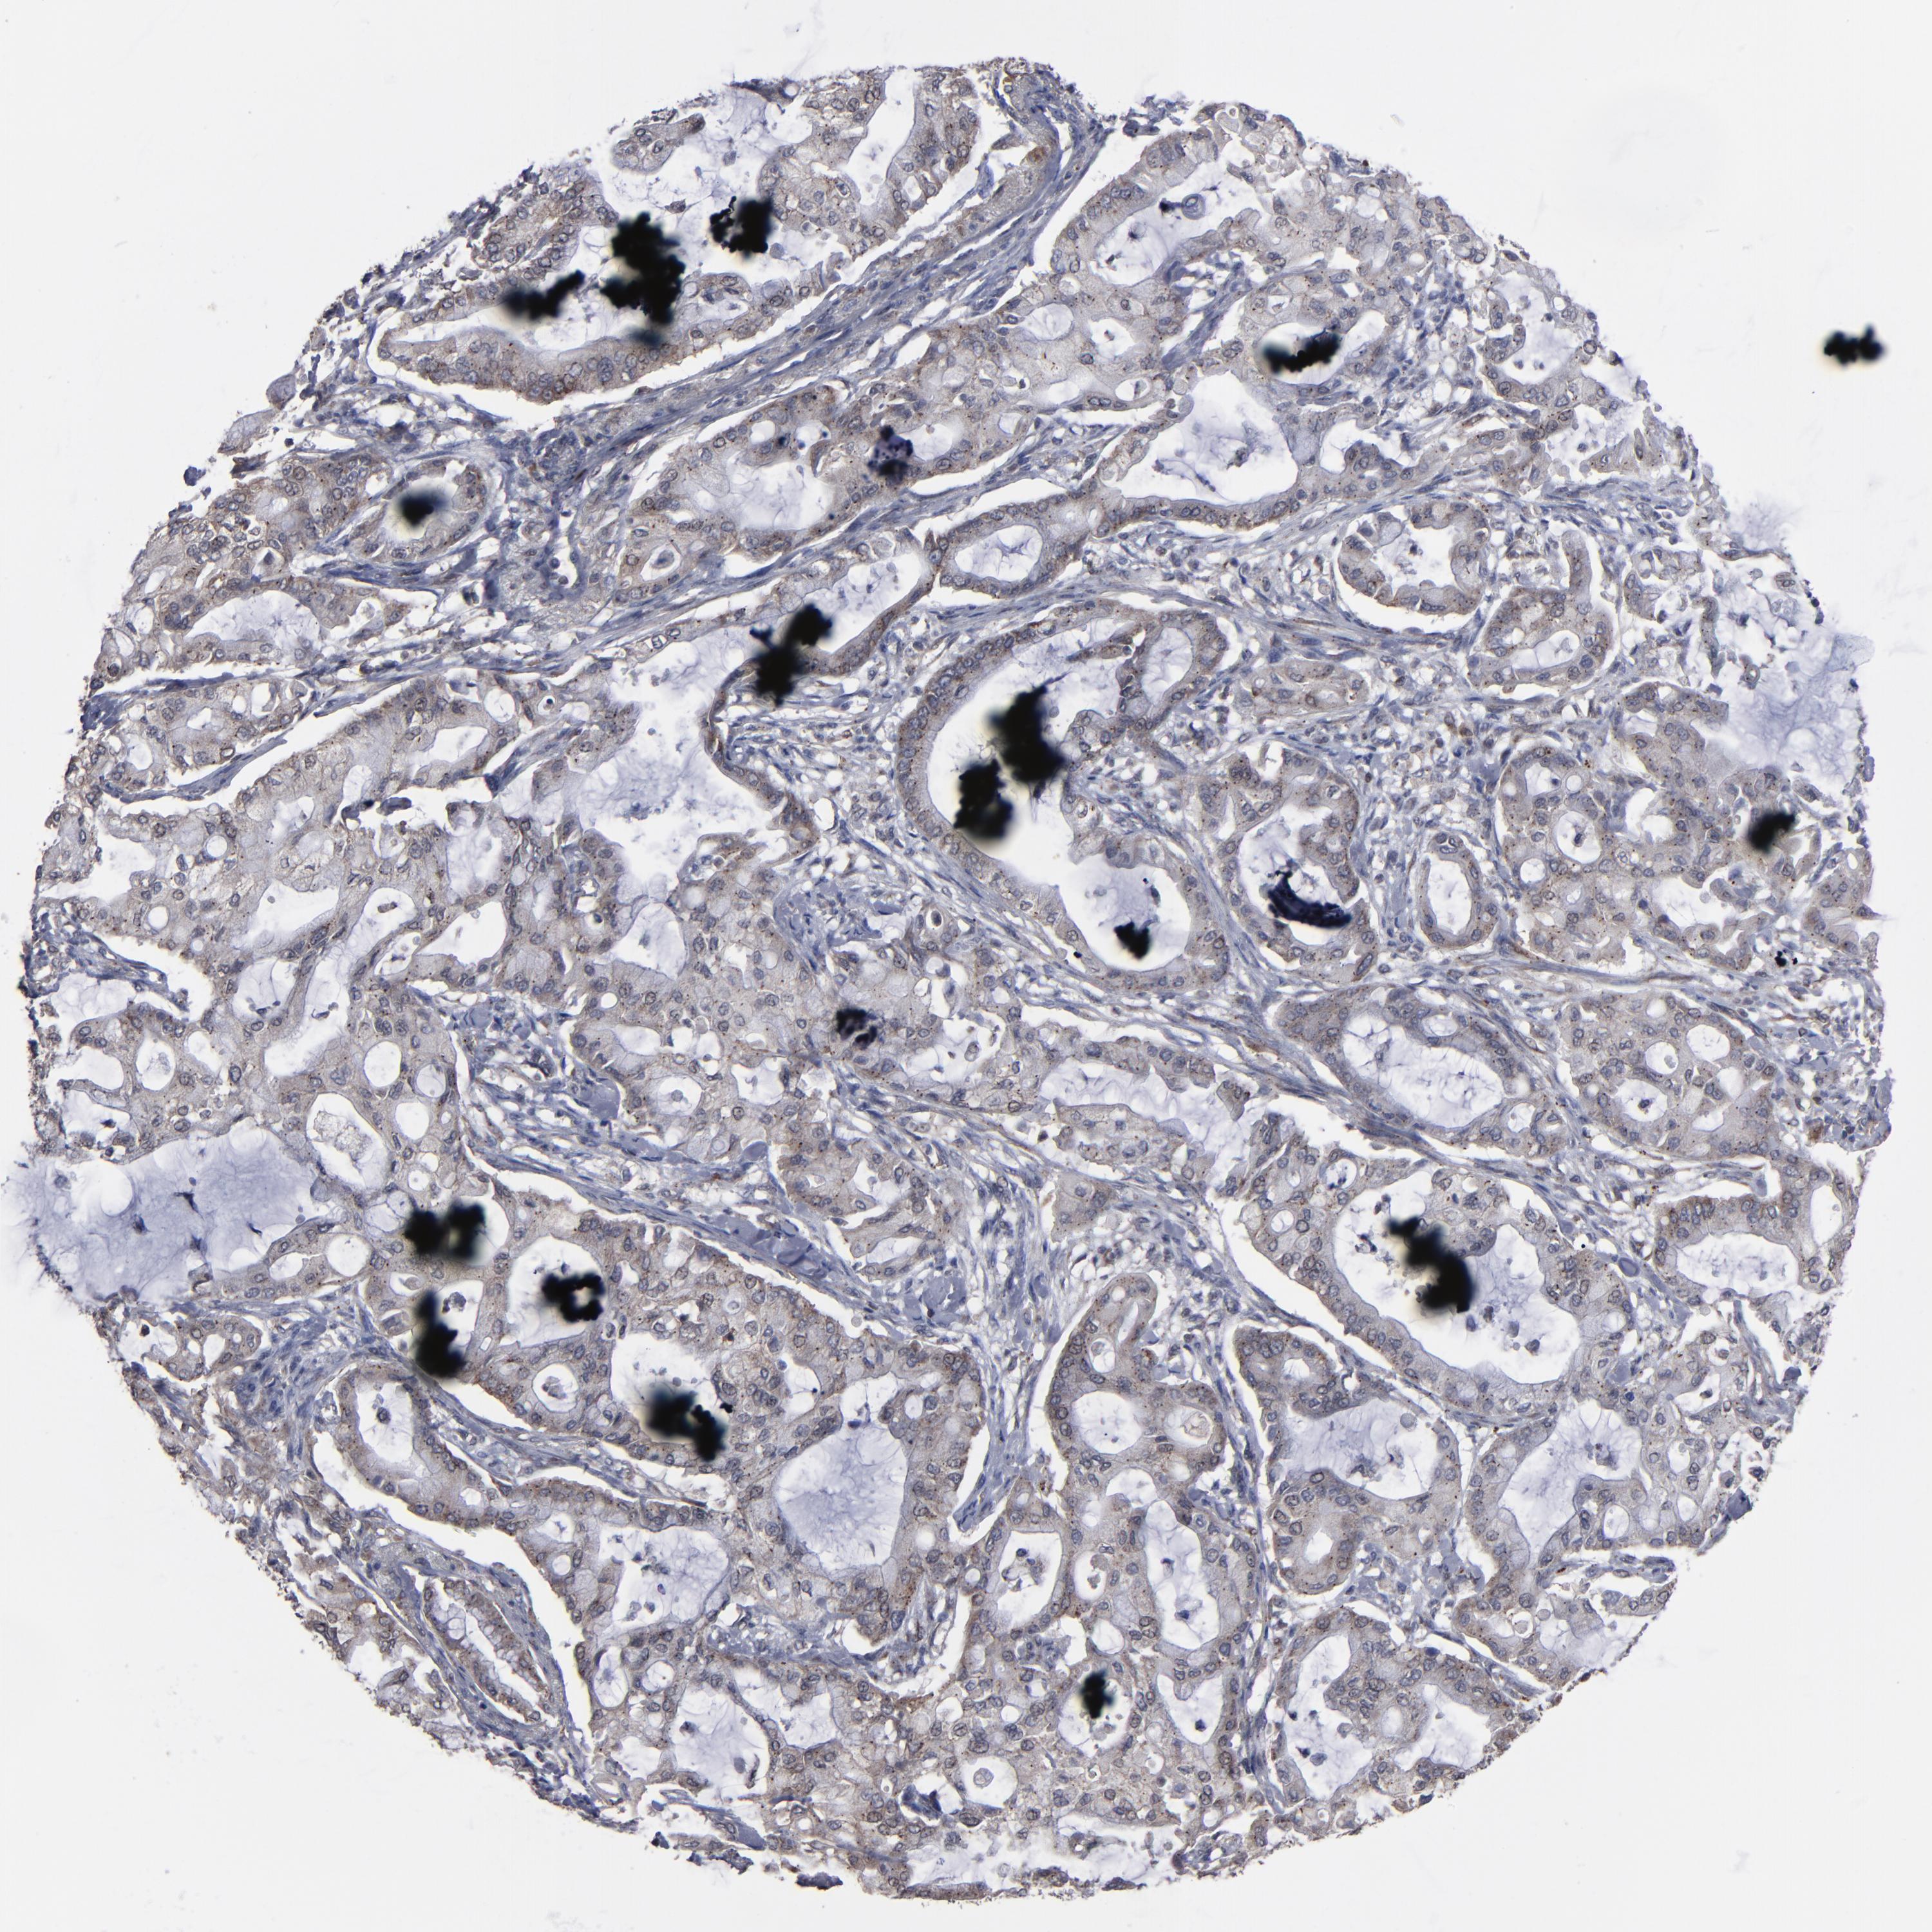

PANCREATIC CANCER - Protein expressioni

A mouse-over function shows sample information and annotation data. Click on an image to view it in a full screen mode. Samples can be filtered based on level of antibody staining by selecting one or several of the following categories: high, medium, low and not detected. The assay and annotation is described here.

Note that samples used for immunohistochemistry by the Human Protein Atlas do not correspond to samples in the TCGA dataset.

Antibody stainingi

Antibody staining in the annotated cell types in the current human tissue is reported as not detected, low, medium, or high, based on conventional immunohistochemistry profiling in selected tissues. This score is based on the combination of the staining intensity and fraction of stained cells.

Each image is clickable and will lead to virtual microscopy that enables deeper exploration of all samples and also displays staining intensity scores, fraction scores and subcellular localization as well as patient and tissue information for each sample.

Antibody HPA002109

Staining

High

Medium

Low

Not detected

Intensity

Strong

Moderate

Weak

Negative

Quantity

>75%

75%-25%

<25%

None

Location

Nuclear

Cytoplasmic/membranous

Cytoplasmic/membranous,nuclear

Adenocarcinoma, NOS

Adenocarcinoma, metastatic, NOS